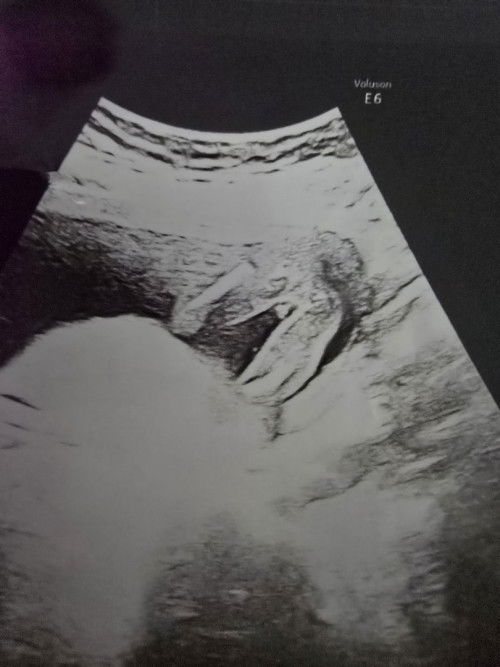

แม่ๆท่านไหน เคยพบถุงการตั้งครรภ์ 1 ถุง ถุงอาหาร 2 ถุงไหมค่ะ ทางนี้ ซาวตอน 5wk พบแบบในรูป แต่ถุงที่ 2 คุณหมอเห็นไม่ชัด นัดอีก 2 week ค่ะ แต่ถุงที่ 1 คุณหมอยืนยันว่าใช่แน่ๆ ถ้าจะเป็นแฝดจริงๆคุณหมอแจ้งไว้ว่าอาจจะมีความเสี่ยงเยอะ#ขอบคณสำหรับคำตอบล่วงหน้านะคะ